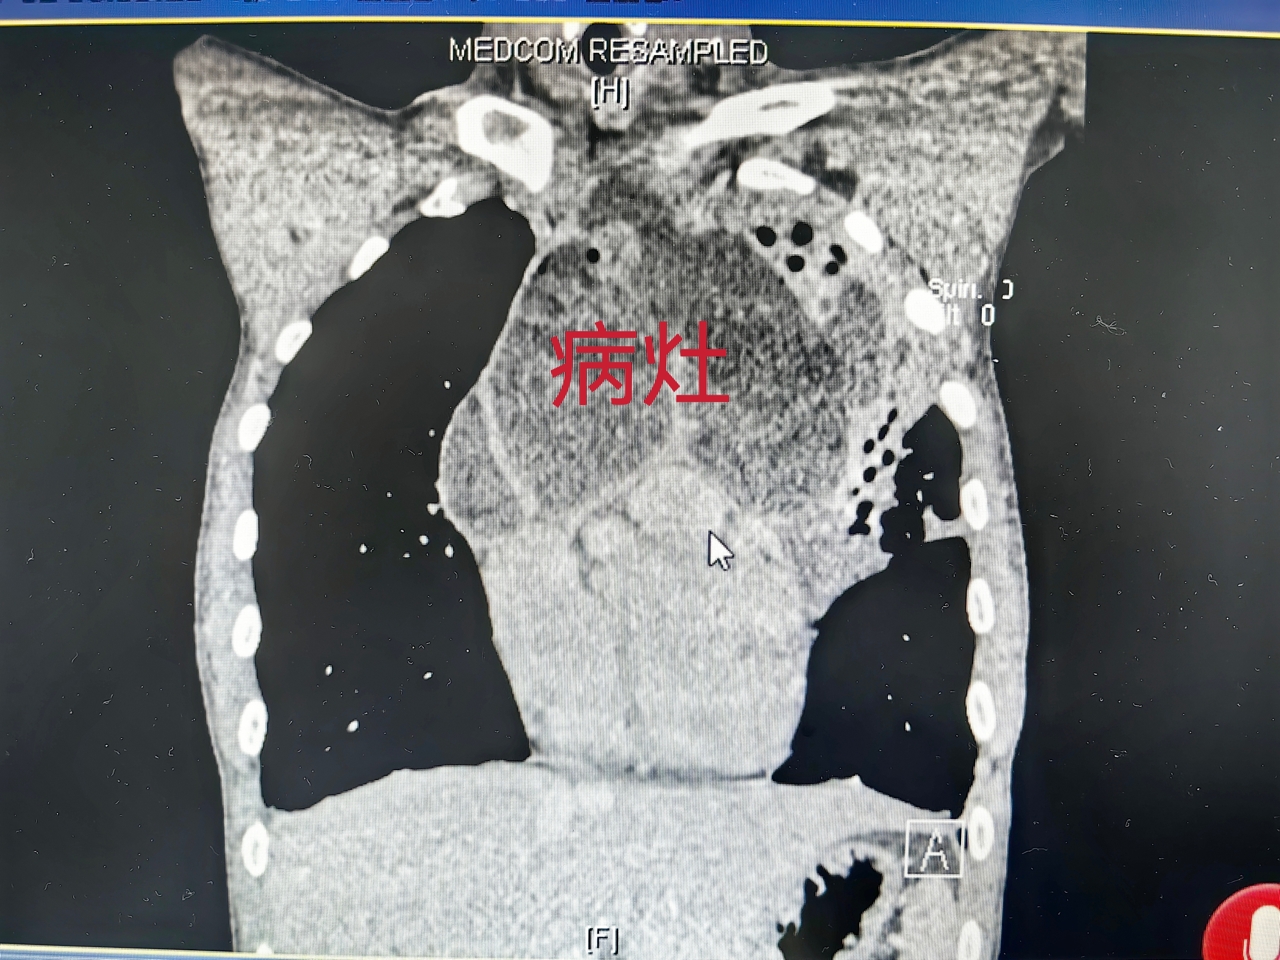

文先生的CT检查显示,他的前纵隔有个直径12cm的巨大占位。

纵隔占位考虑畸胎瘤,且肿瘤可能与左上肺的气管相通,一躺低即有少量囊液或肿瘤组织进入病人气道,造成剧咳。久而久之,造成左上肺严重感染,并通过气道影响到其他肺叶。通过多次送检,患者肺结核的指标均为阴性。针对原先抗真菌感染治疗效果不佳,专家也调整了抗感染方案。

文先生的病情稳定以后,复查胸部CT显示前纵隔肿瘤较前缩小了。